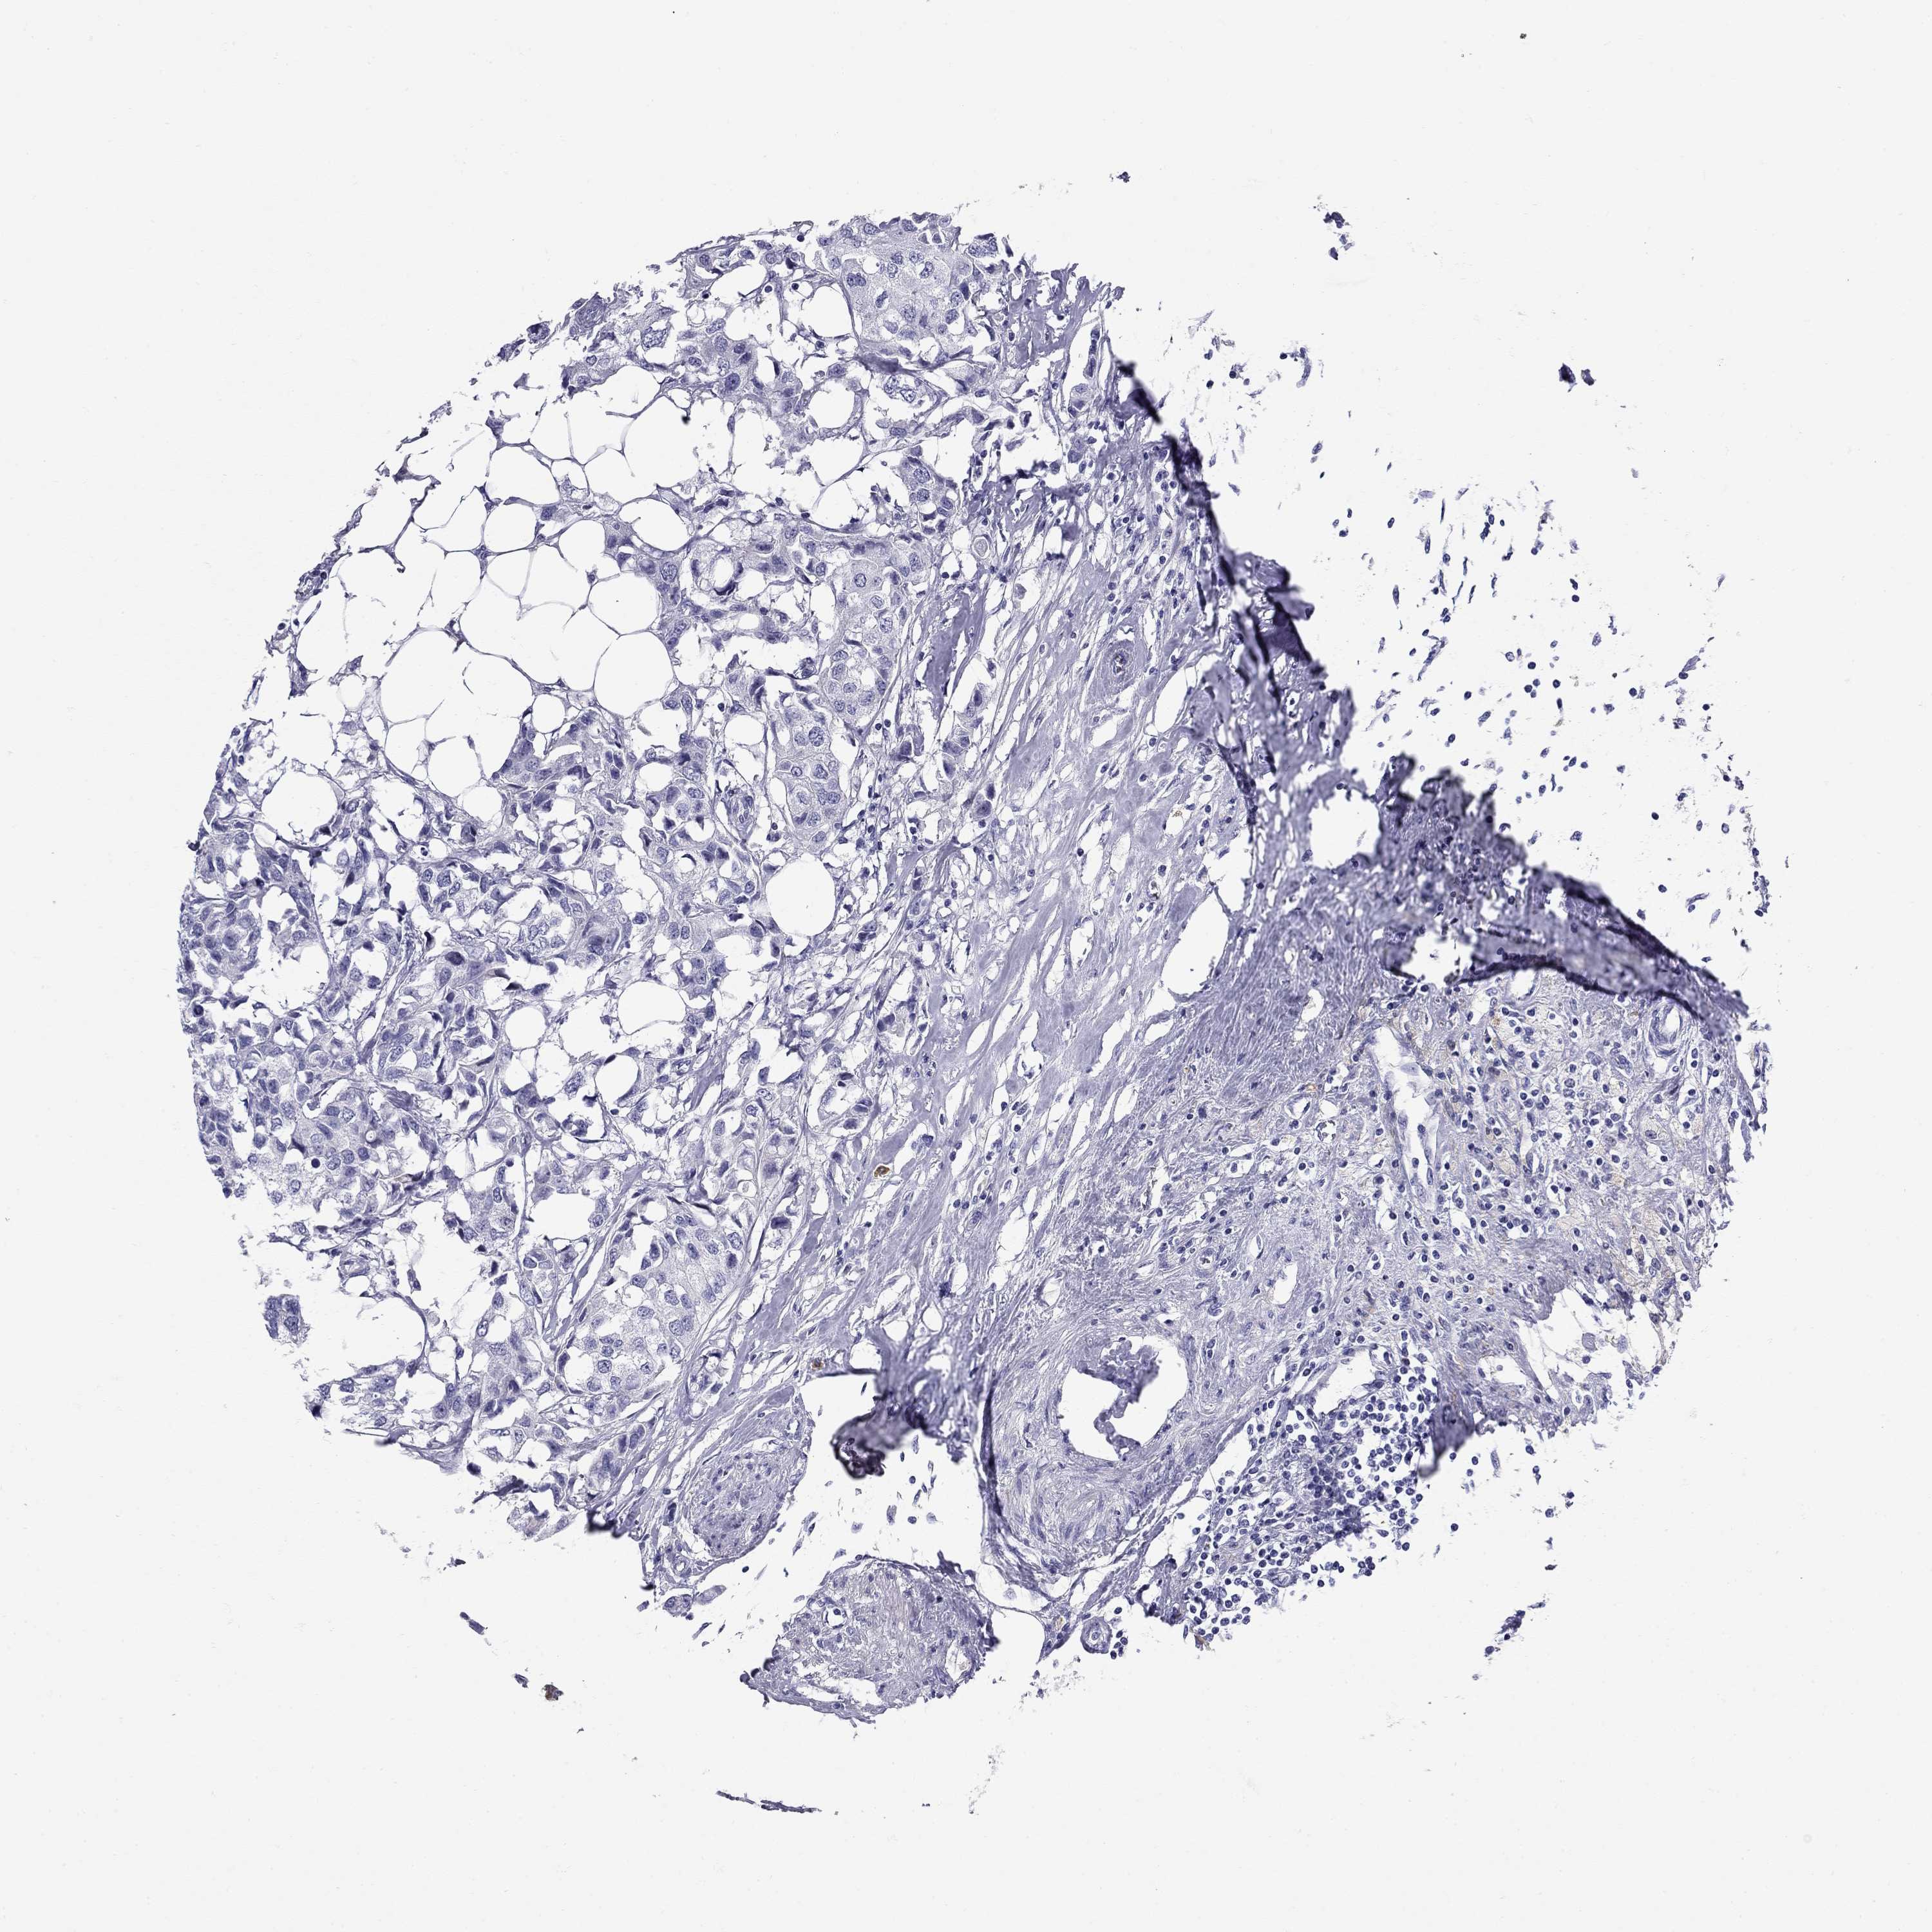

BRCA TCGA BRCA VALIDATION PROTEIN EXPRESSION

Breast cancer

Human cancer